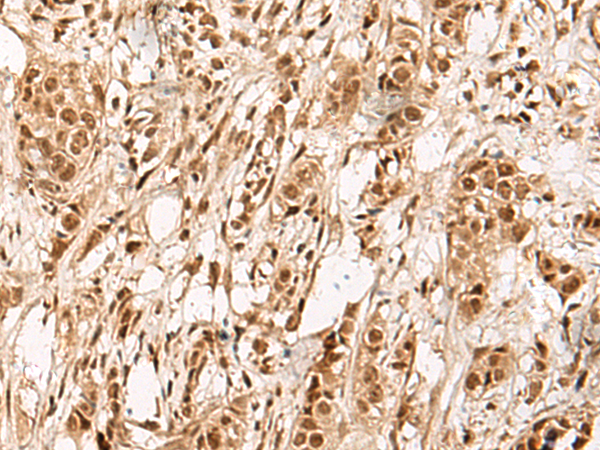

IHC (Immunohistochemistry)

(Immunohistochemistry of paraffin-embedded Human breast cancer tissue using ZBTB43 Polyclonal Antibody at dilution of 1:90(×200))